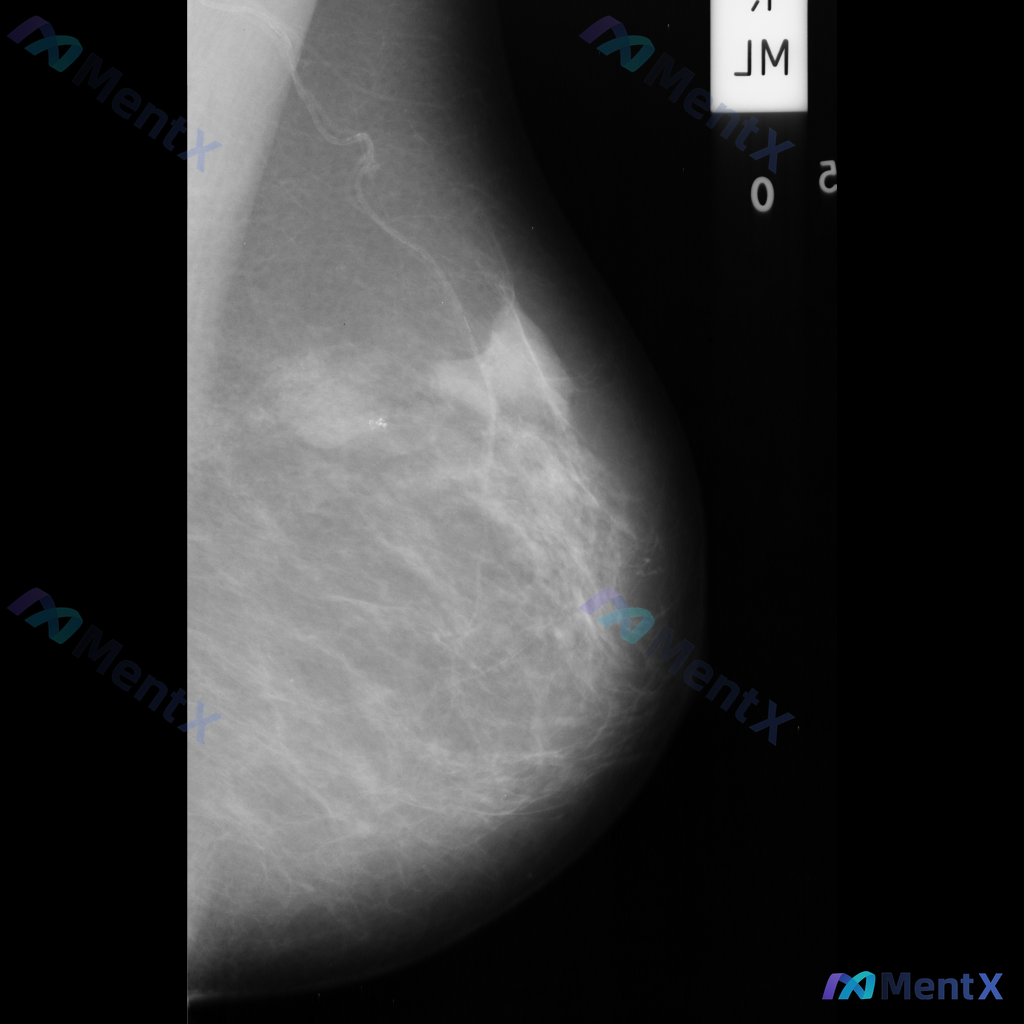

整理到一份单侧乳腺钼靶的影像资料,想和大家讨论一下读片思路: 影像背景与征象 - 背景:不均匀致密型乳腺 - 主要异常: 1. 乳腺中央及中下部可见一片边界模糊的斑片状/不规则形密度增高区 2. 该密度增高区域内,似乎存在乳腺正常小梁结构的牵拉或紊乱 3. 中下部偏乳头方向,有一组较为集中的、形态不...

整理到一张乳腺钼靶影像的读片资料,分享给大家讨论。 影像表现:左乳中上象限可见一不规则形高密度致密影,边界部分模糊;内部可见细小、簇状分布的钙化影;同时局部乳腺腺体结构有轻度扭曲和牵拉。 目前需要判断的是,这组表现更支持哪一类情况?